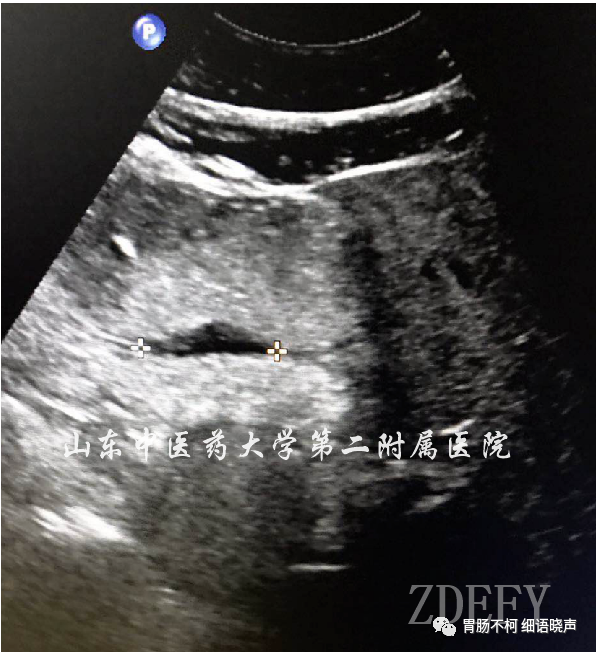

“平地挖坑征”是良性溃疡的征象。良性溃疡是宛若平地的胃壁炎症基础上的破损凹陷,就像直接在平地挖了个坑,故名“平地挖坑征”。溃疡底部较平整。典型病例如下: